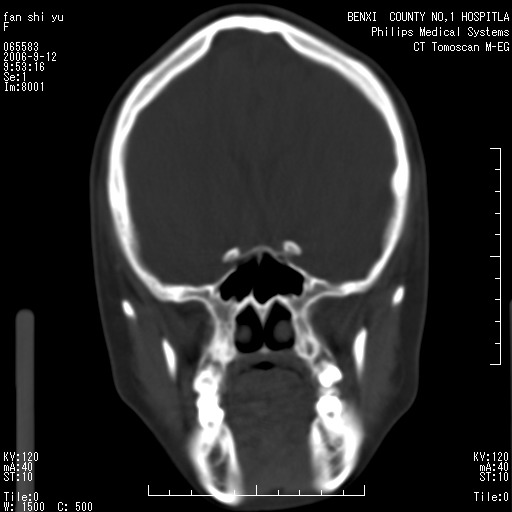

标题: CT4607:看看这个头颅冠状位。

女,22岁,自觉头顶部质硬包块.

巨大蛛网膜粒压迹。

巨大蛛网膜粒压迹